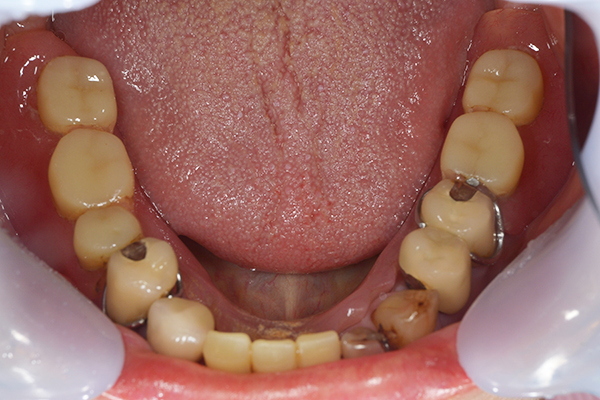

ケース2(自費の総入れ歯と部分入れ歯)

上下の入れ歯が外れやすくなったということでいらっしゃいました。 顎の骨はしっかりしていましたので、精密な型取りさえすればしっかりした入れ歯がつくれると思いました。 また下には6本歯が残っていましたが、虫歯になっている歯もありました。 かぶせ物のなかで大きな虫歯があった歯があり、1本だけ残せない状態でした。

上の入れ歯は確かに吸着は甘くなっていました。 また下の入れ歯はバネの一部が壊れており、安定感がなくなっていました。

精密な型取りの後、噛み合わせのチェックをしていきました。 かぶせ物も同時に作っていきました。

歯を並べた後、かぶせ物のフレーム作ってもらいました。先に歯を並べて理想の位置を決めておくことが大切です。

完成した入れ歯とかぶせ物です。 入れ歯への寛容度が高い患者様でしたので、 金属は使用せず、プラスチックのみで上は仕上げました。 下顎も歯は1本減ってしまいましたが、しっかり 入れ歯が維持できる様な構造にしました。

お口の中に入れた状態です。 見た目も最初とほとんど変わることなく作成できました。 維持や吸着に関しても問題ないようでした。

年齢 80歳・女性

主訴 上下の入れ歯が外れやすくなった

治療期間 3ヶ月

治療費 .メタルボンドクラウン:550,000円

.義歯:990,000円(税込、上下)

治療方針 長年使ってきた義歯の人工歯が磨耗し、臼歯部での咬合がすくなくなり、入れ歯の安定も悪くなり、あたりどころが悪くなって痛みが出ている。 そのため、入れ歯を上下作りかえる必要がある。

治療内容 過去に治療を行ったことのある歯が再度虫歯になってしまっているところがあり、すでに残せない状態にまでなっていたため、歯を一本抜歯した。 その後、かぶせ物と入れ歯を同時に作成していった。

特記事項 歯を抜いた後は、2〜3ヶ月歯ぐきの回復を待ってから入れ歯を作るため、待機期間があります。その間、古い入れ歯を調整しながらそのまま使うか、新し物をつくっておく必要があります。ただし、入れ歯は保険治療で作成する場合、6ヶ月は新しいものが作れないという決まりがあるので保険で全て作りたい場合は注意が必要です。